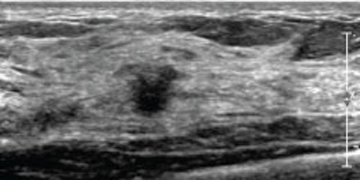

Ultrasonido Especializado en Mama

Estudios avanzados de imagen de la mama por medio de ondas de ultrasonido.

• Patología Benigna y Maligna

• Implantes Mamarios

• Mama Infantil y Adolescente

• Mama Masculina

• Second Look Ecográfico

• Doppler Mamario